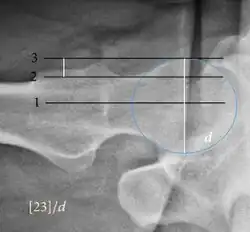

| Crossing ratio |

|

Percentage of acetabular walls crossing. Normal acetabulum is oriented in anteversion. Its value ranges from 15 to 20° in the equatorial plane of the acetabulum and decreases gradually towards the acetabular roof, where normal values range from 0 to 5°. Retroversion of the upper part of the acetabulum has been related with pincer type impingement. In radiography the presence of a "crossover sign" is produced when the posterior wall of the acetabulum crosses the anterior wall before reaching the acetabular roof. It is a sign of acetabular retroversion and it has been linked with overcoverage and pincer impingement. Nevertheless, this sign has been described in 6% of the normal population. Therefore, more important than its presence is the percentage of crossing. | <20%